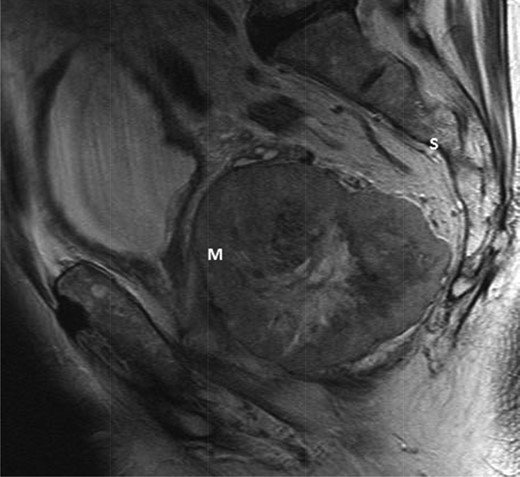

An elderly man in his seventies presented to the Urology department with two episodes of acute urinary retention. There were no rectal symptoms and rectal examination revealed an enlarged prostate. He underwent a laser transurethral resection of prostate during which a large palpable pelvic mass was noted. The subsequent urgent MR pelvis revealed a large tumour in the mesorectum arising from the anterior rectum 10 × 8.5 cm (Figs 1 and 2). A transrectal ultrasound and biopsy were performed; histology revealed a spindle cell tumour, with positive immunostains for CD117 and DOG1 with 5 mitoses per 50 high power fields. This was confirmed to be a locally advanced high-risk GIST.

T2-weighted sagittal image demonstrating a large mass (m) anterior to the sacrum (S) and posterior to the bladder.

T2-weighted axial showing the same mass lying adjacent to the anterior wall of the rectum (*).